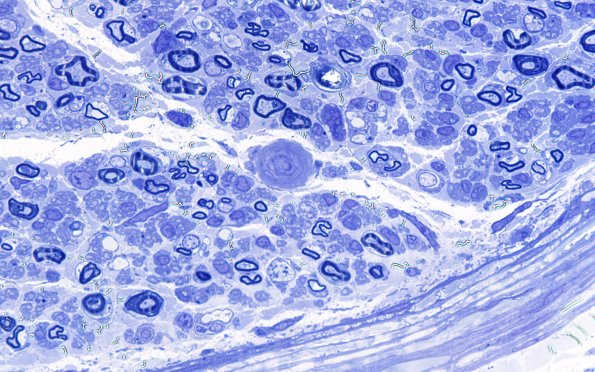

5B4 (Case 5) Plastic 100X 3

Many endoneurial vessels show marked thickening of their walls.